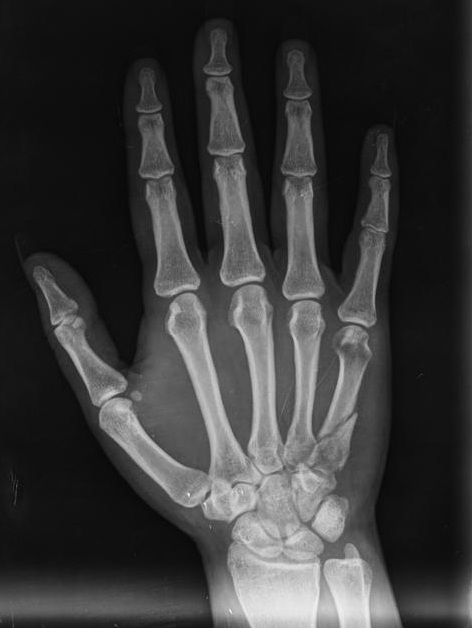

TA deep learning-based solution for detecting bone fractures from X-ray images. It utilizes CNN architectures like ResNet50 to classify bone types and identify fractures efficiently. The model is trained on 20,000 X-ray images and employs a two-step classification process for accurate diagnosis, aiding medical professionals in improving patient care